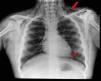

La radiografía de tórax demostró enfisema subcutáneo y neumomediastino (fig. 1). Al completar el estudio con TAC torácica para descartar alteraciones parenquimatosas, se detectó aire en el canal raquídeo limitado al espacio epidural (fig. 2).